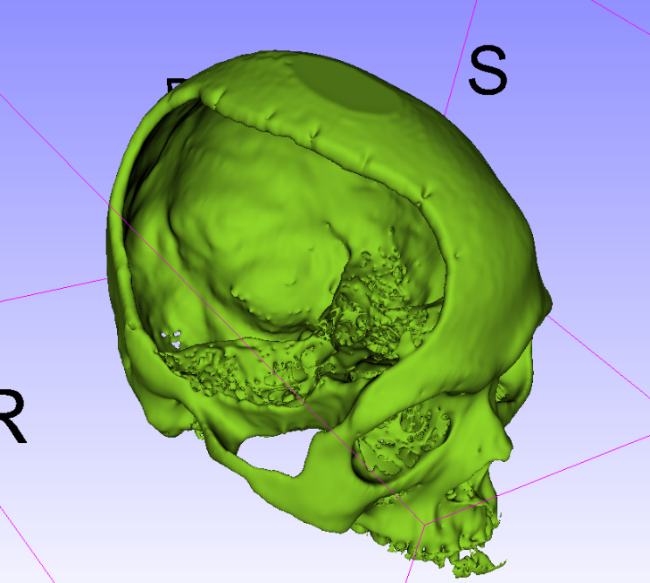

术中情况: